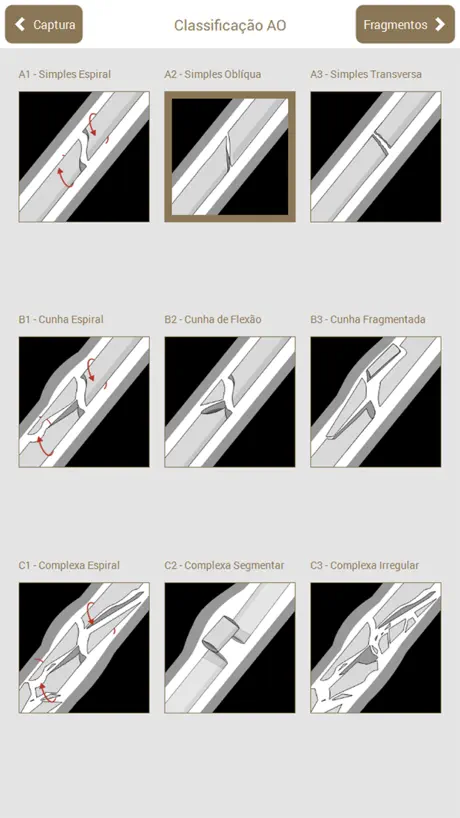

Osteotrauma é um aplicativo que auxilia no planejamento de cirurgias ortopédicas.

O objetivo do planejador é auxiliar o médico em todas as etapas do planejamento de cirurgias ortopédicas em fraturas de ossos longos.

No aplicativo, é possível executar os mesmos passos que são feitos em um planejamento manual: Escolha da radiografia, Classificação AO, Seleção e recorte das partes, Redução, Planejamento dos Implantes, Preenchimento da ficha do paciente, Geração de relatório e Edição manual do relatório gerado (que pode ser exportado em PDF).

O objetivo do planejador é auxiliar o médico em todas as etapas do planejamento de cirurgias ortopédicas em fraturas de ossos longos.

No aplicativo, é possível executar os mesmos passos que são feitos em um planejamento manual: Escolha da radiografia, Classificação AO, Seleção e recorte das partes, Redução, Planejamento dos Implantes, Preenchimento da ficha do paciente, Geração de relatório e Edição manual do relatório gerado (que pode ser exportado em PDF).